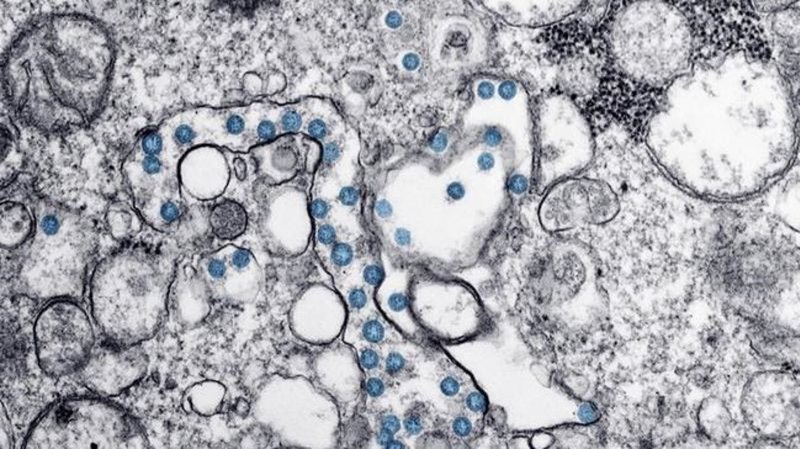

Eight people test positive for COVID-19 at B.C. mink farm, outbreak declared

BURNABY, B.C. - A health authority has declared a COVID-19 outbreak at a mink farm after eight people at the operation in British Columbia's Fraser Valley tested positive for the disease. Fraser Healt...